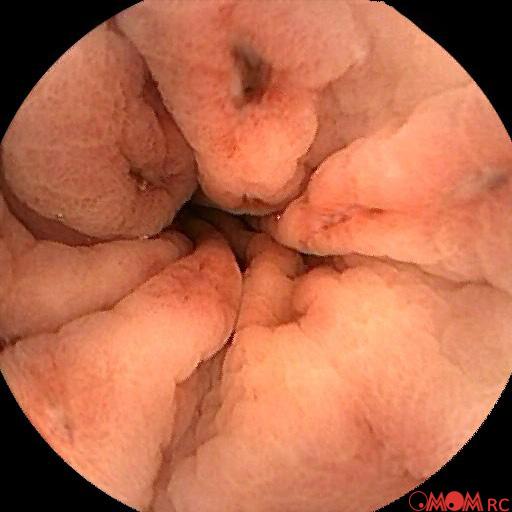

Typical Findings

Polyp Erosion Gastritis Ulcer